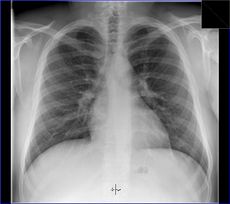

Lékařské využití

Poté, co Röntgen objevil využití pro pozorování kostních struktur, se rozvinulo jeho užívání v lékařském snímkování. Rentgenové záření může být využito pro zobrazení detailů kostí a zubů (skiagrafie), popřípadě za pomoci vhodných technik i ke zkoumání měkké tkáně (denzitografie, subtrakční skiagrafie, tomografie). Radiologie je specializovaný obor lékařství využívající rentgenového záření v diagnostice. Toto je pravděpodobně nejčastější využití rentgenového záření.